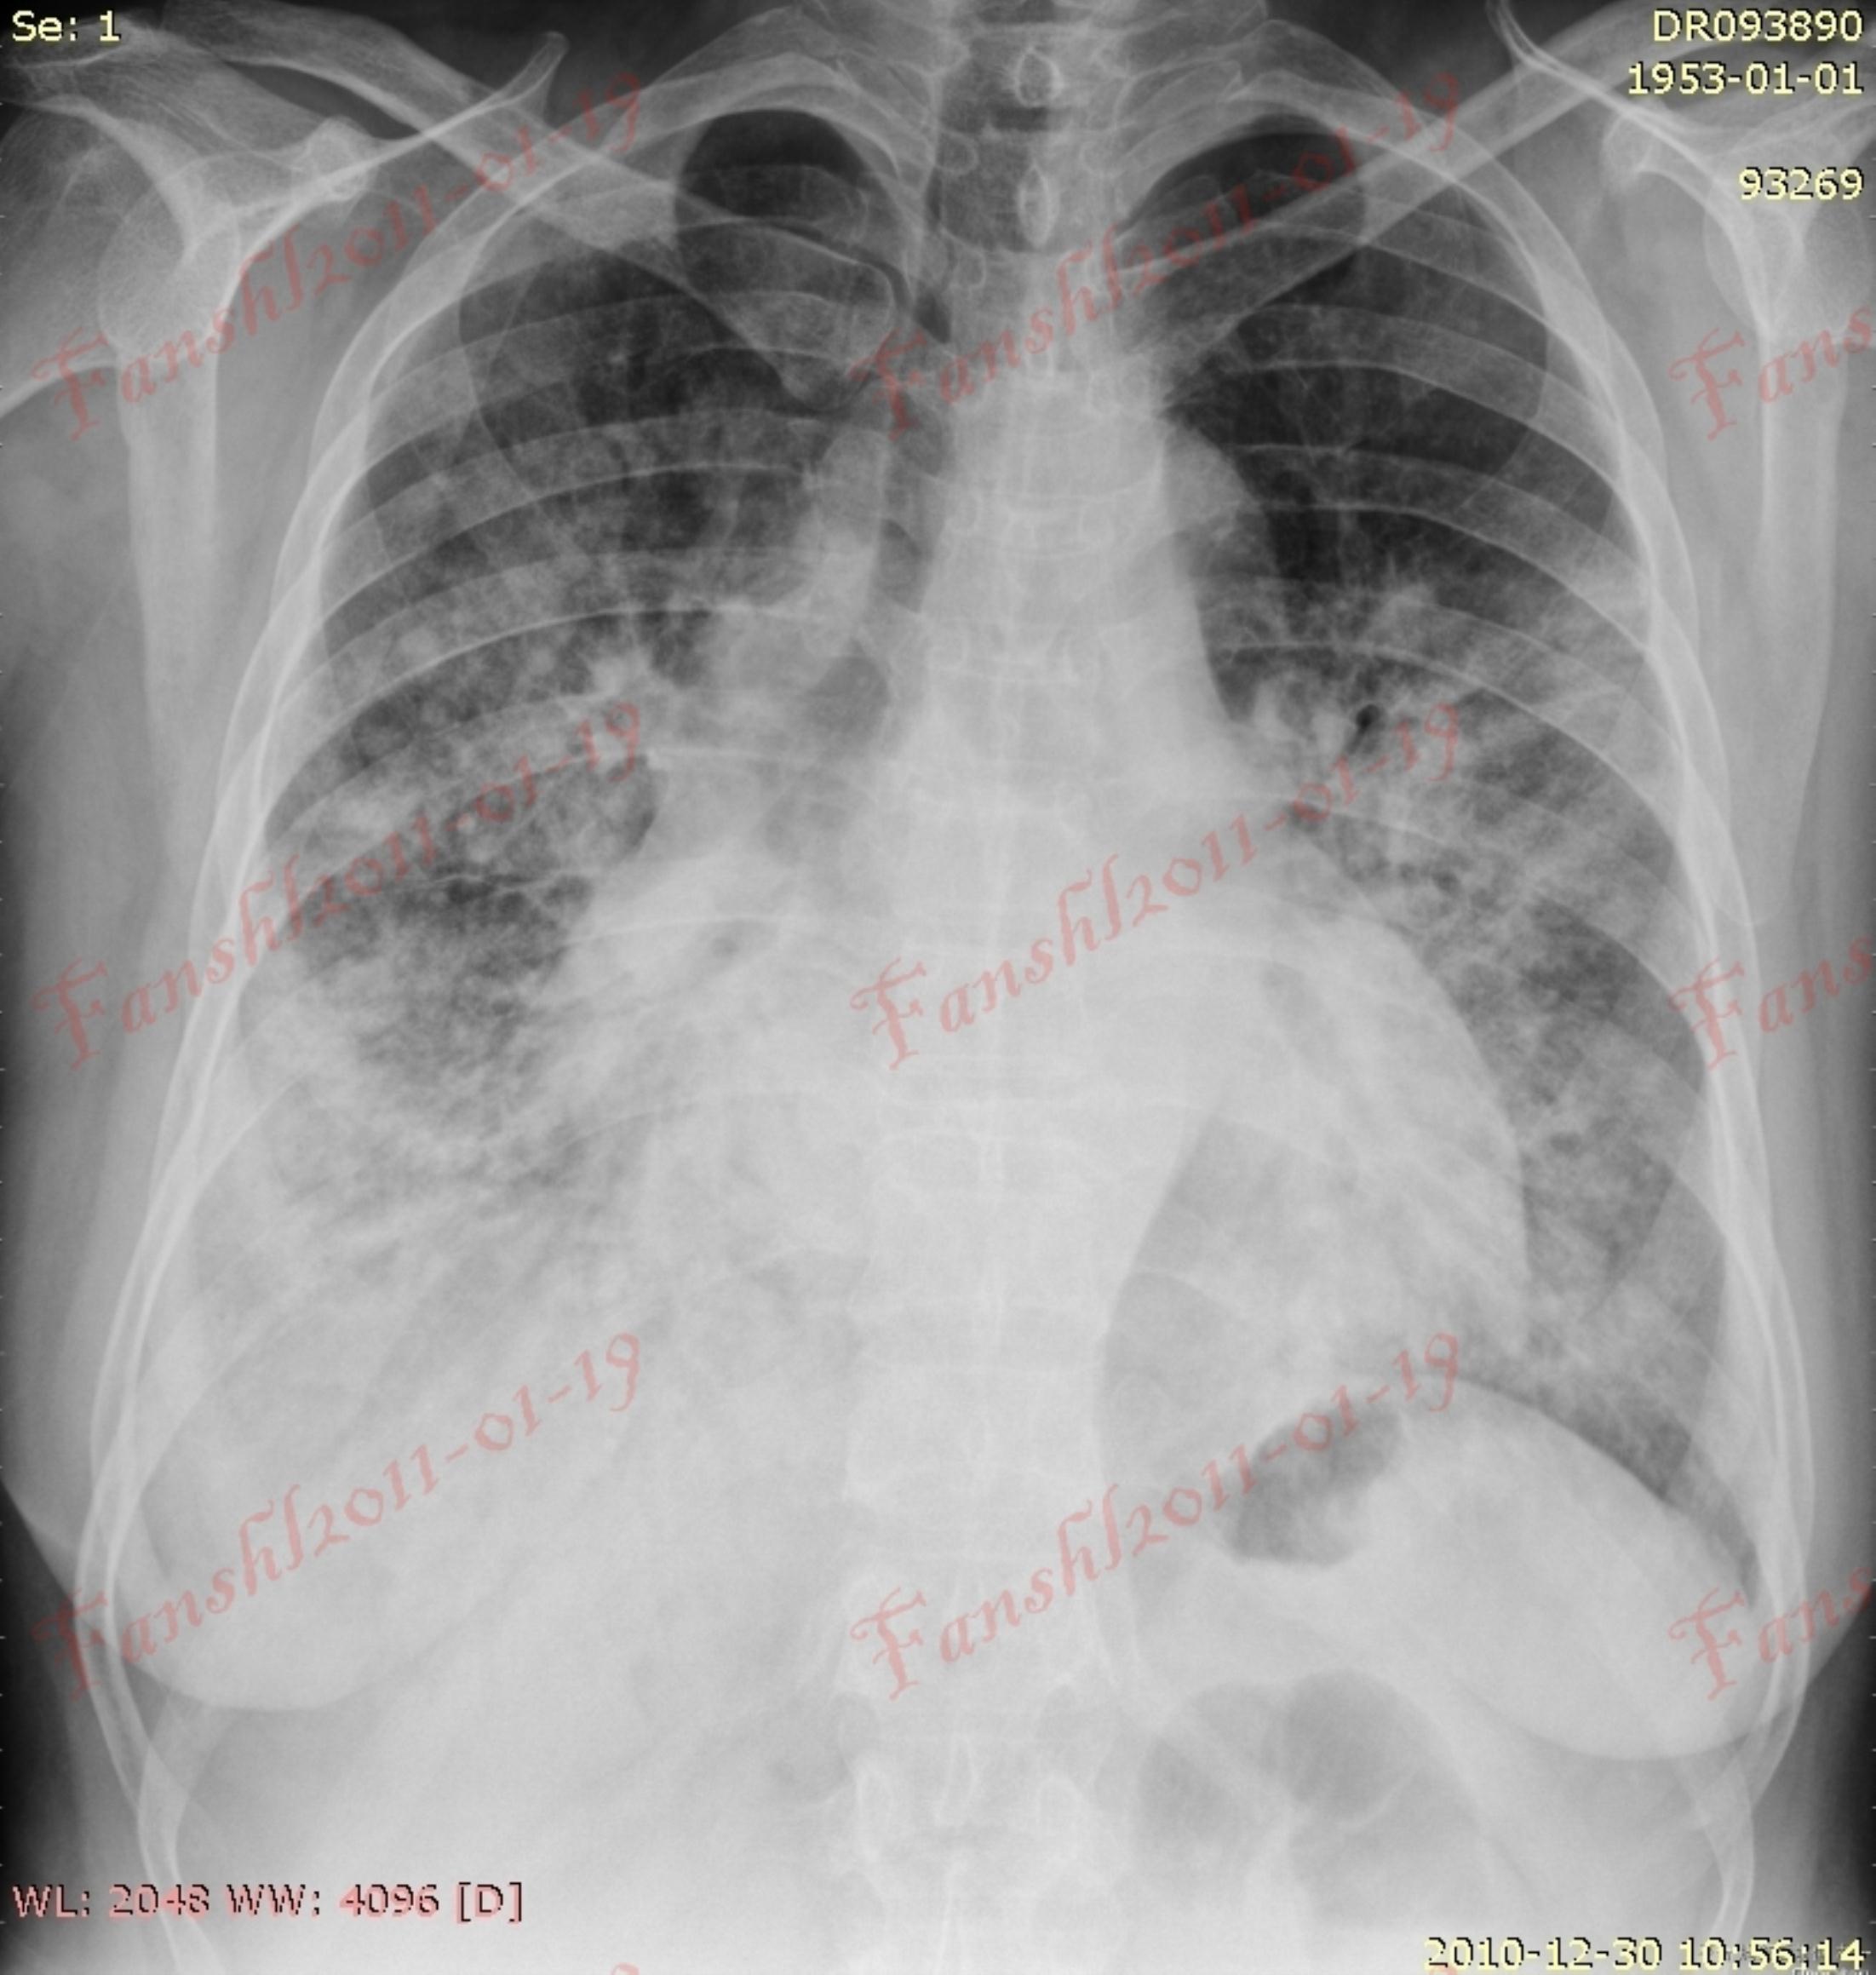

肺部感染经典影像征象

ct31147:肺水肿心功不全合并肺感染

肺部感染 ct 太难学?看完这篇不信你还不会!

查房手记不明原因肺部感染死亡一例

肺部感染ct读片,这6个坑你一定踩过

肺部感染拍片图片

肺部感染图片真实

肺部感染胸片

严重肺部感染ct图片